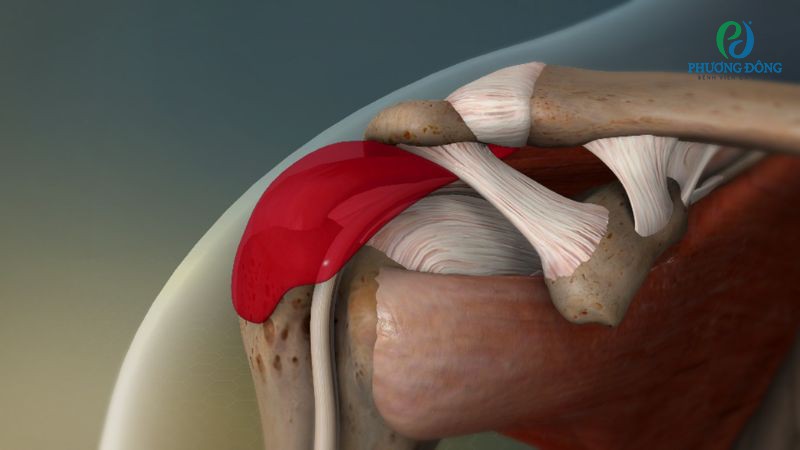

Rách cơ chóp xoay vai

Rách cơ chóp xoay vai là tình trạng các cơ quay khớp vai bị tổn thương một phần hoặc toàn phần. Nguyên nhân có thể đến từ hoạt động lặp đi lặp lại trong thời gian dài, làm tổn thương gân cơ chóp quay hoặc chịu lực va đập mạnh.

Rách cơ chóp xoay vai là tình trạng cơ quay khớp vai bị tổn thương một hoặc toàn phần